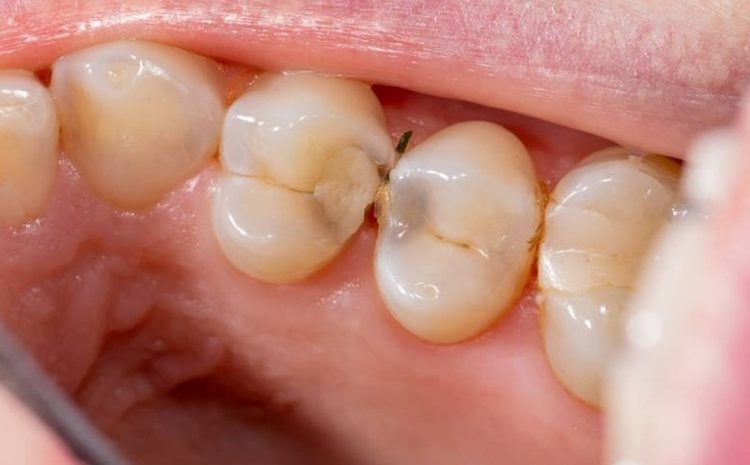

In another situation, when you have a toothache, you go to the hospital for a check-up and find out that it may be due to deep tooth decay, causing the root of the tooth to become infected, inflamed and painful.

After examination, the doctor determined that the tooth nerve was infected and required root treatment. There were many cavities in the mouth and multiple fillings were needed.

This type of tooth decay can be caused by not paying attention to oral hygiene, not cleaning and cleaning your teeth regularly, and having regular check-ups.